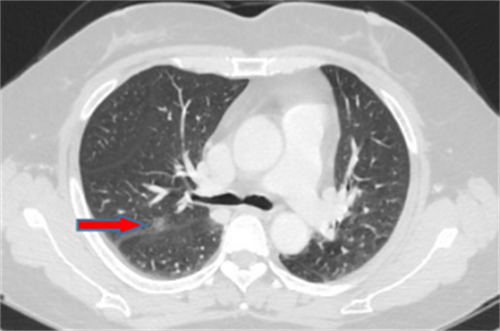

李先生,45岁,发现右上肺结节2年,近期长大,术后病理诊断肺结节为炎性假瘤。